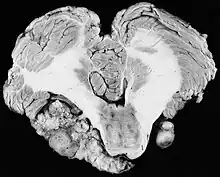

There have been cases of tumors that were actually asymptomatic until very large and at a critical stage. Tumor growth rates are highly variable: some small VSs (perhaps 50%) do not grow at all; some few grow for a time and then shrink; some appear dormant but suddenly grow rapidly. In general, although studies differ, VSs that grow are slow-growing at an average rate of 1.2 to 1.9 mm per year. IAC tumors that grow beyond 1.5 cm in diameter expand into the relatively empty space of the cerebellopontine angle, taking on the characteristic 'ice-cream-cone' appearance seen on MRIs. As 'space-occupying-lesions,' the tumors can reach 3 to 4 cm or more in size and infringe on the facial nerve (facial expression) and trigeminal nerve (facial sensation). Advanced hearing loss and spells of true vertigo may occur. Very large tumors are life-threatening when they press on the cerebellum or cause brainstem compression. Late symptoms of very large VS include headache, nausea, vomiting, sleepiness, mental confusion and eventually coma.[3][4]

In the early 1900s the mortality rate for VS surgery was in the range of 75 to 85%. Surgeons typically delayed invasive intervention as long as possible as a last resort. Harvey Cushing (1869–1939) is known as 'the father of neurosurgery for VS.' His basic study published in 1917 was entitled Tumors of the Nervus Acusticus and the Syndrome of the Cerebellopontine Angle. Cushing perfected the retrosigmoid surgical approach, and by doing suboccipital craniotomy and subtotal removals he was able to reduce mortality to 4% by 1931. Cushing worked at Brigham Hospital in Boston. An equally famous specialist for VS at Johns Hopkins in Baltimore was Walter E. Dandy (1886–1946), a former pupil of Cushing who advocated total tumor removals. In 1931, he reported a complete removal with preservation of the facial nerve.